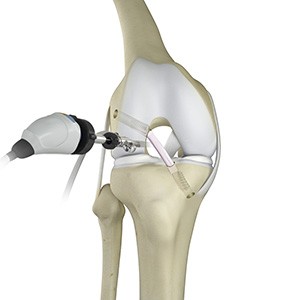

Knee Arthroscopy

Knee arthroscopy is a common surgical procedure performed using an arthroscope, a viewing instrument, to diagnose or treat a knee problem. It is a relatively safe procedure and you will usually be discharged from the hospital on the same day of surgery.